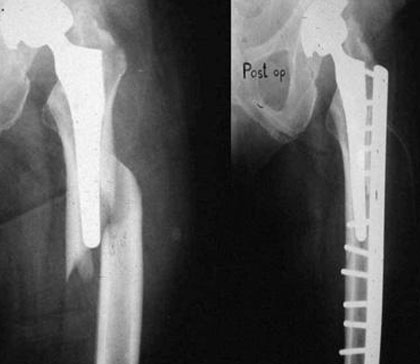

Periprosthetic fractures are fractures that occur in association with an orthopaedic implant, most often used for joint arthroplasty or fracture fixation. They are associated with significant morbidity and increased mortality in some cases.

The incidence of periprosthetic fractures appears to be increasing as a result of increasing patient longevity, more demanding activity levels that persist into advanced age for some patients, and as a result of the increasing rate of revision arthroplasty which accompanies increasing patient longevity.